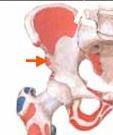

DESPRINDEREA NUCLEULUI SECUNDAR DE CALCIFICARE A TROHANTERULUI MIC

Traumatism la o gimnasta de 13 ani

Desprinderea nucleului de osificare secundar

al trohanterului mic pe care se insera tendonul

psoasului iliac

Confirmare radiologica